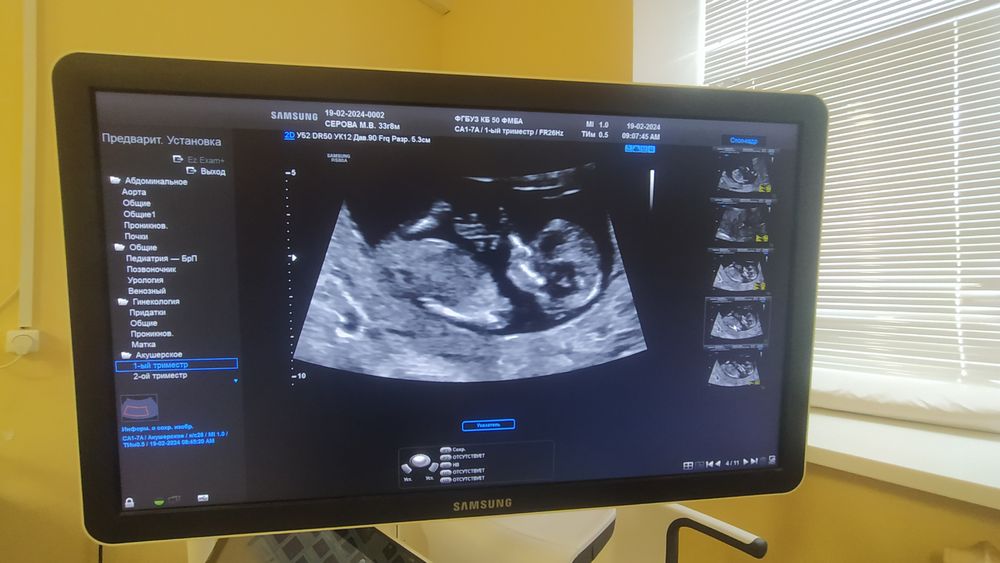

12.5 недель 1 скрининг .

Ну по этой фотографии похоже на мальчика) там определяют по этому хвостику, если он вертикально - мальчик, если горизонтально расположен - девочка)

Не знаю, по мне так "хвостик" параллельно со спиной. Девочка

Девочки-знатоки, посмотрите🤗 НИПТ Panorama